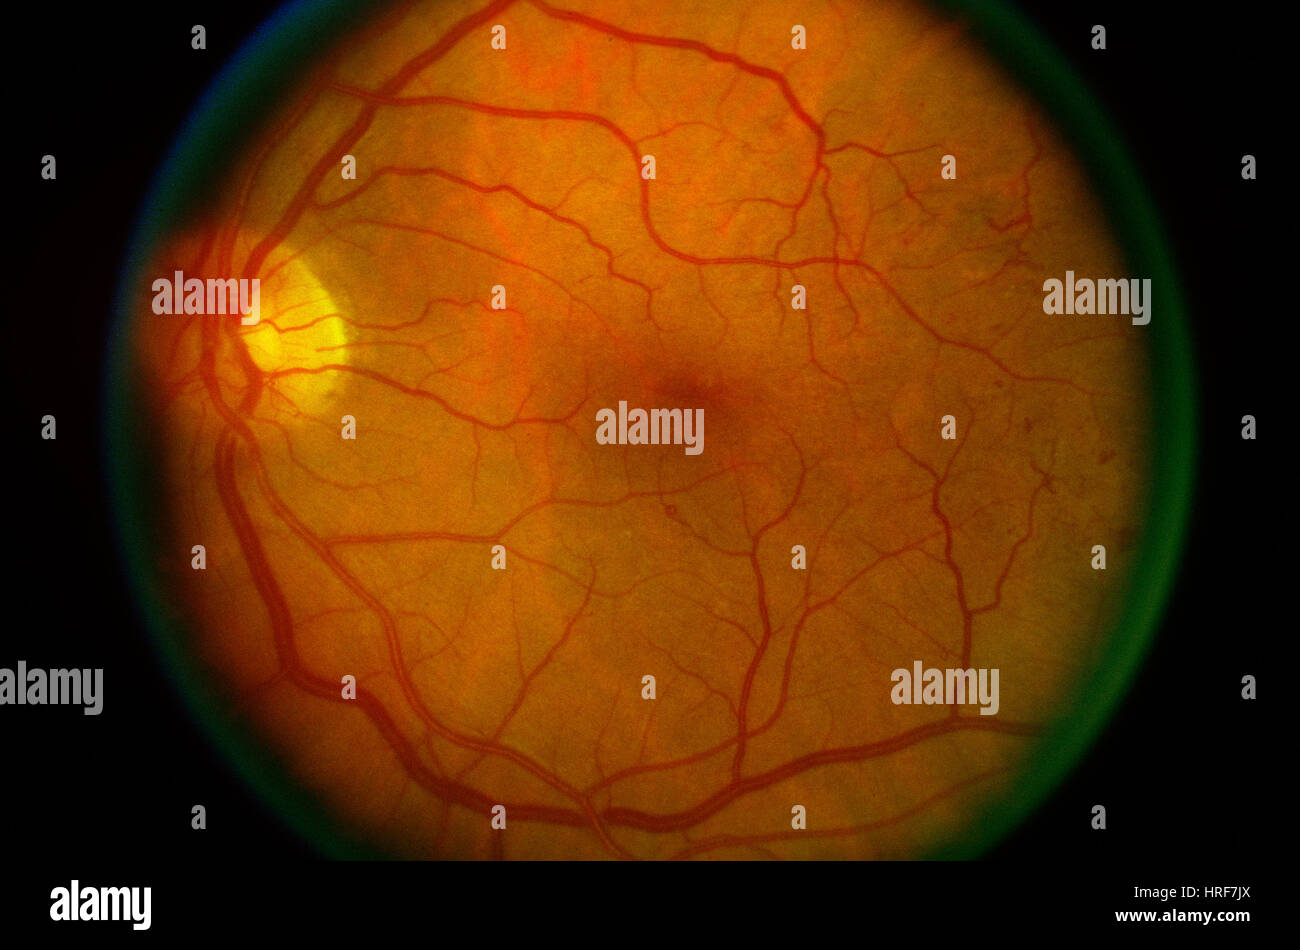

Diabetic Retinopathy Stock Photohttps://www.alamy.com/image-license-details/?v=1https://www.alamy.com/stock-photo-diabetic-retinopathy-134944962.html

Diabetic Retinopathy Stock Photohttps://www.alamy.com/image-license-details/?v=1https://www.alamy.com/stock-photo-diabetic-retinopathy-134944962.htmlRMHRF7JX–Diabetic Retinopathy